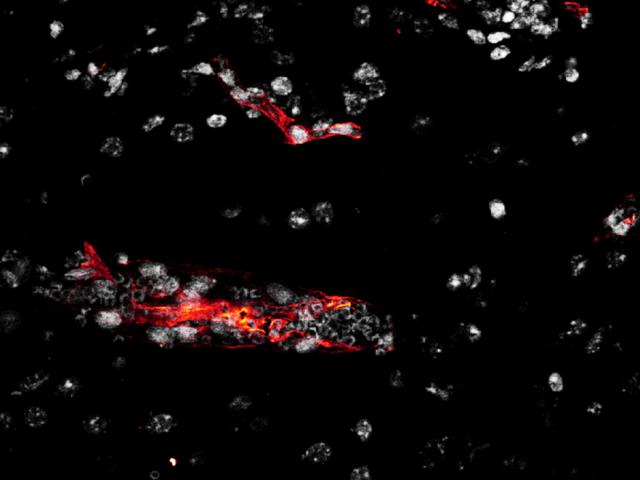

Brain Section

Brain Slide